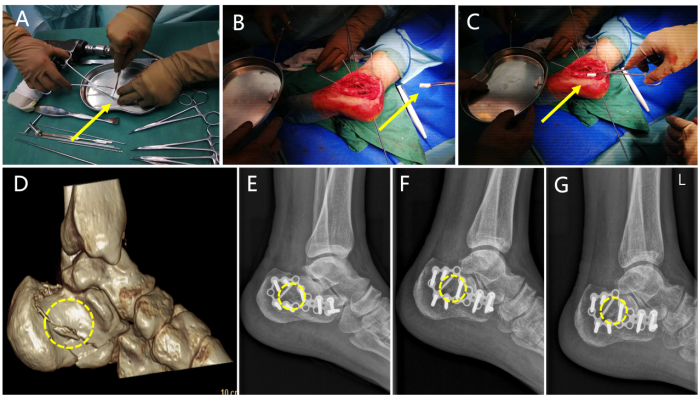

本研究的核心在于对新型低温3D打印技术制备的 Mg-PLGA-TCP 复合多孔支架(商品名:Bongolle®)的临床转化效果进行系统评估。该支架通过材料比例与结构的精密设计,实现了力学性能与生物活性的双重优化。

前瞻性多中心临床研究在全国 8 个临床机构同步开展,共纳入 174 例因疾病或创伤导致需行骨移植的四肢骨折患者(如胫骨平台骨折等),并采用随机对照设计,将患者分为 Mg-PLGA-TCP 治疗组与商业化 β-TCP 对照组,系统评估了新型含镁复合多孔支架在骨修复中的安全性与有效性。